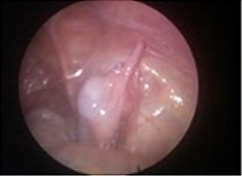

A testis which is non- palpable can be intraabdominal or atrophic or sometimes difficult to palpable in an obese child. Laparoscopy is the best answer for these testes as it is not only diagnostic as well as therapeutic. It can locate the testis and at the same time testis can be brought down to its normal position.

Intra-abdominal testis